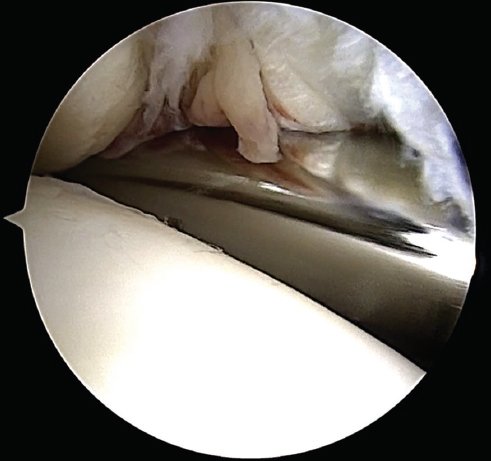

A los 10 días de la lesión fue sometido a una artroscopía anterior de tobillo, en la cual se evidenciaron fragmentos condrales libres y lesión condral en el astrágalo a nivel de la axila anteromedial de 10 mm sin estructura ósea adherida. Además, se confirmó una ruptura completa del fascículo anterior superficial del complejo deltoideo (tibio astragalino) y se corroboró la lesión sindesmal mediante la introducción del palpador (Fig. 3).

Figura 3. Introducción de la punta de un rasurador en la diástasis de la sindesmosis durante la artroscopía.